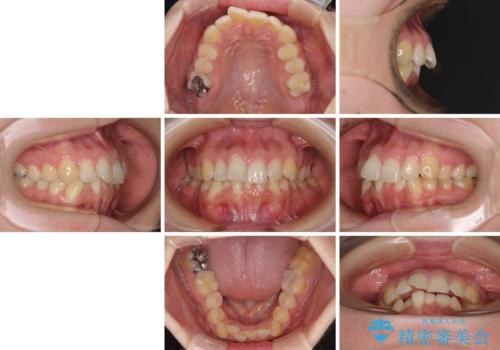

- 前歯のデコボコで前方に出ていることを気にして来院された患者様です。

上顎前歯が捻れて前方に飛び出しており、下顎前歯もそれに沿うようにデコボコとなっていました。

IPR(歯と歯の間を削る処置)によりスペースを獲得して上下顎前歯のデコボコを改善し、飛び出している前歯が引っ込むように設定し、インビザラインにて矯正治療を行うこととしました。